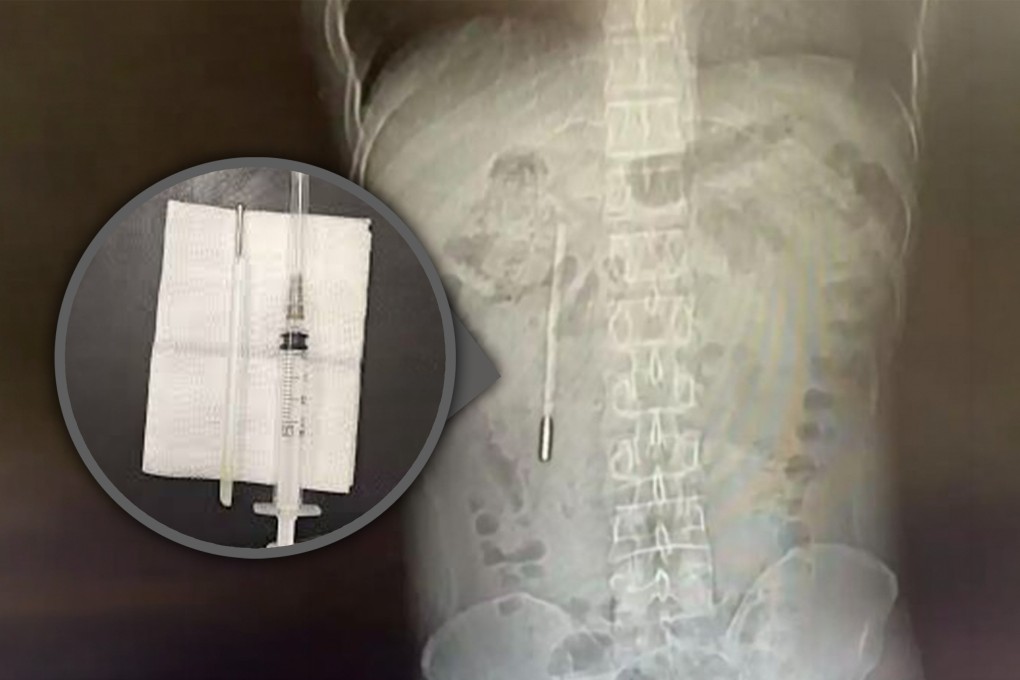

Surgeons perform emergency operation to remove offending object; extracted device remains intact but temperature measurements had faded

A scan revealed a foreign object in his duodenum, which doctors highly suspected to be a mercury thermometer.

As the tip of the thermometer was pressing directly against the intestinal wall, it posed a high risk of perforation and severe internal bleeding.